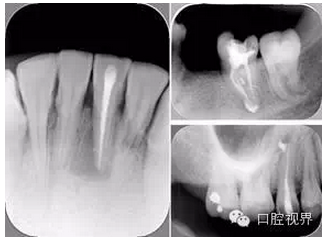

左圖和上圖為干髓治療后牙齒,齲齒疏通后進行根管充填。

如圖為塑化加根充處理后牙齒 X 線片。

6. 鈣化

常見有修復(fù)性鈣化和增齡性鈣化。下面為根管鈣化 X 線片。

右圖及下圖為器械折斷的 X 線片。箭頭處示折斷器械。